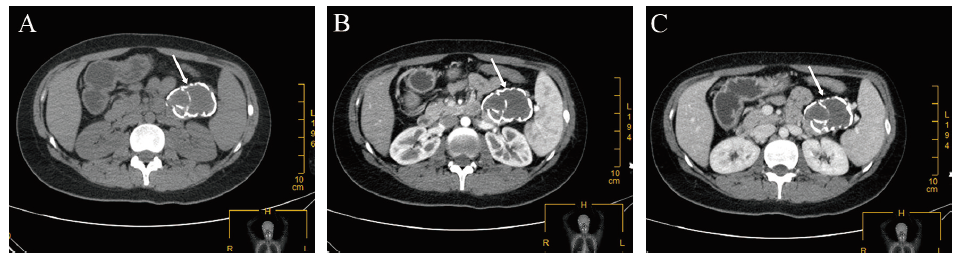

患者女,29岁。因胸骨后疼痛伴憋闷不适3个月余于2021年3月2日入院。体格检查未触及腹部包块。实验室检查示癌胚抗原0.94 μg/L,糖链抗原199为30.5 U/mL,癌抗原125为12.5 U/mL。腹部增强CT示脾胰间隙囊性占位,约5.4 cm×3.7 cm,增强扫描未见明确强化,病灶与胰腺前缘分界不清,初步考虑血肿机化或假性囊肿或囊腺瘤钙化相鉴别;脾脏增大,约占8个肋单位(图1)。既往无腹部手术史和外伤史。

图1 一例SPN患者术前CT检查

注:A为CT平扫;B为CT 增强动脉期;C为CT 增强门脉期;箭头指示囊肿。

SPN作为一类低度恶性肿瘤,其临床表现无特异性,多因体检发现而就诊。部分患者可出现上腹疼痛、黄疸、呕吐、腹泻、腹部包块及体质量下降等非特异性症状体征[5]。SPN常在CT、MRI检查时被发现,其CT特征为囊肿较大,呈实性,边界清晰,内部少见分隔,囊肿有外膜包裹,部分患者可见钙化,密度混杂,增强后可见实性外膜增强,内部可见强化突起,呈现为“浮云征”[6]。本例主诉为“胸骨后疼痛伴憋闷”,此临床表现更具迷惑性,曾被误诊为反流性食管炎。因SPN肿瘤无特异性指标,且本例腹部增强CT提示为囊性病变,但无“浮云征”,使SPN诊断更为困难。